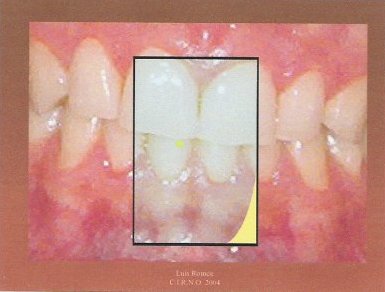

5.- Repetimos el paso anterior pero lateralizando para la izquierda.

6.-Despegamos el papel en el que queda marcados la línea de referencia y los dos puntos y lo adherimos sobre una plantilla previamente fabricada.